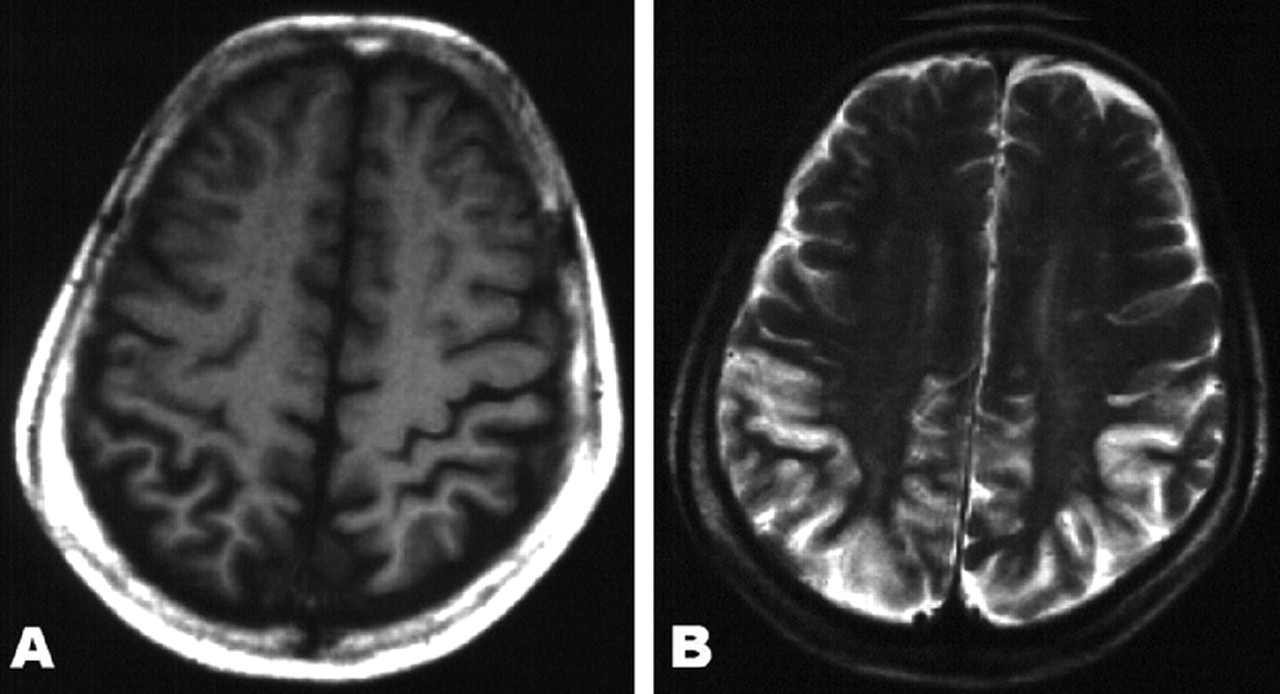

一个70岁的右手女人离开hemineglect开发。她的记忆、洞察力和判断力是正常的,但是穿衣失用症,计算力缺失,观察和Balint综合症,符合后皮质性痴呆(PCD)。1MRI显示parieto-occipital皮质的萎缩(图,一个),皮质hyperintensity diffusion-weighted成像(驾车)共存(见图B)。2可能的诊断克雅氏病(CJD)由世界卫生组织的标准是由脑脊液的14-3-3蛋白升高,随后无着丝粒的缄默症,和脑电图变化。阿尔茨海默病以来,库贾氏症等神经退行性疾病可能表现为PCD,醉酒驾车的MRI和CSF 14-3-3蛋白可能有助于区分这些病因,避免从一个病人传播库贾氏症的风险。